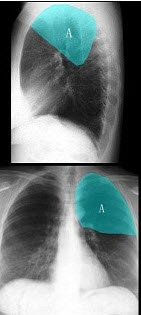

A.正常压迹

男,10月。有时哭闹。X线检查如图,最可能的诊断为()

A.畸胎瘤

B.胸腺瘤

C.婴幼儿胸腺

D.右上肺不张

E.神经母细胞瘤

点击查看答案